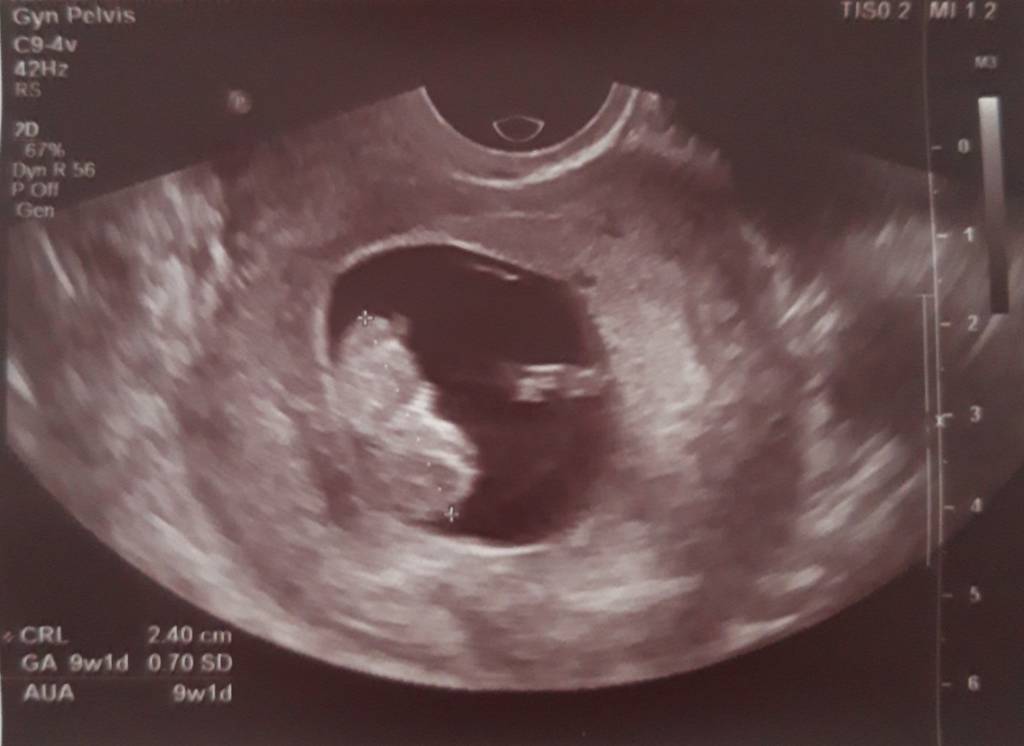

To i ja się pochwalę moim szczęściem i prześle ciążowe fluidy~~~~~~~[emoji177][emoji177][emoji177]

Wczoraj miałam wizytę u gina termin om zgodny z usg na 20.06.[emoji3] Dzidzia ma 2.40 cm serduszko bije 174bmp.[emoji7]

Ale glukoza wyszła mi za dużo bo aż 106 [emoji853]zakaz jedzenia słodyczy owoców, soków masakra tych słodyczy to mogę nie jeść i tak nie jem ale nie wiem jak sobie poradzę bez owocy[emoji37][emoji37] w tygodniu powtarzam glukozę i zobaczę co wyjdzie. Oto moja kruszynka.[emoji7][emoji7][emoji7]Zobacz załącznik 917229